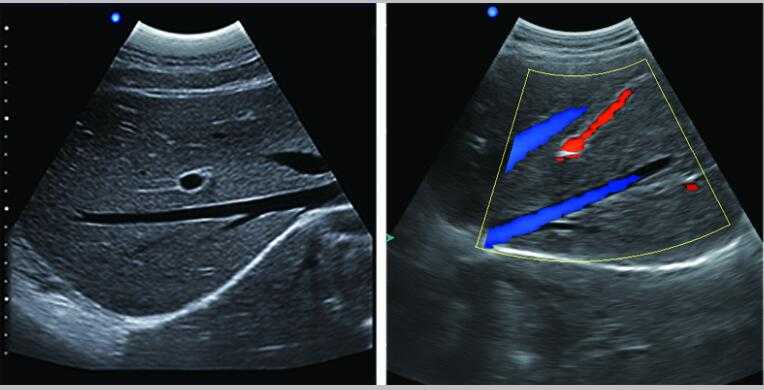

彩色多普勒

采用智能圖像處理技術(shù)1.組織諧波成像技術(shù) 2.噪聲抑制斑點(diǎn)技術(shù) 3.多波束并行處理技術(shù)等

7.應(yīng)用:腹部、婦科、產(chǎn)科、心臟、血管和小器官、泌尿科、肌肉骨骼、兒科等